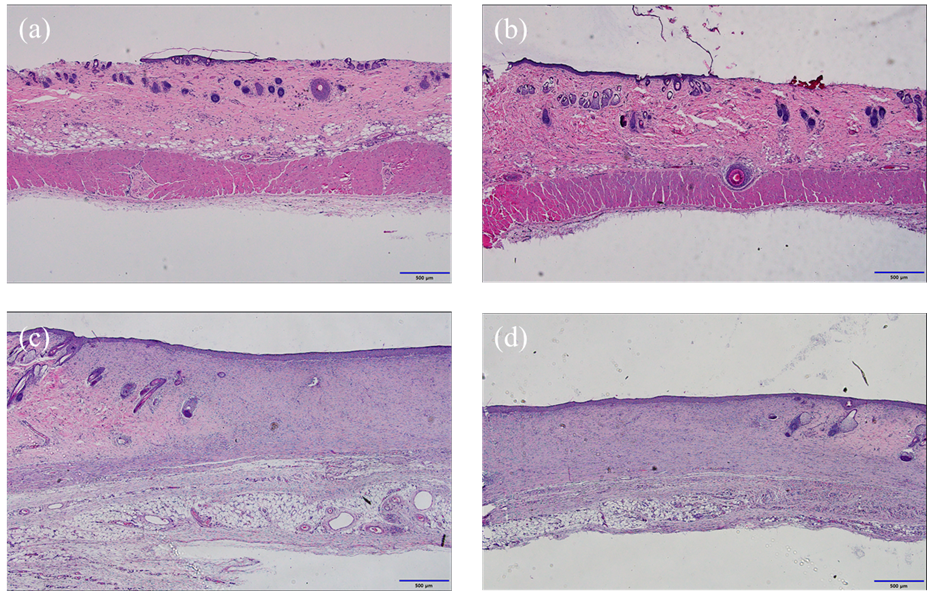

Hydrogel films were prepared using 10% w/w PVA dissolved in 8% ethanol, with the addition of 1–4% w/w of either dextrin or guar gum. BAC was included at a concentration of 5% w/w. The formulations were cast into films and assessed for their film formation time, tensile strength, elasticity, and swelling behavior. In vitro permeation studies were performed using excised rat skin and Franz diffusion cells to evaluate BAC delivery. For in vivo analysis, full-thickness wounds were created on the dorsal skin of rats, followed by daily application of the test films. Wound closure was monitored over 12 days, and tissue samples were analyzed histologically on the final day.

Dextrin-based hydrogels produced stronger, more durable films with higher swelling ratios, while guar gum-based films dried more rapidly and offered greater initial flexibility. The addition of PEG1500 improved the stretchability of the films, and oleic acid facilitated BAC penetration through the skin in a dose-responsive manner. In animal studies, both types of FFH dressings significantly enhanced wound closure compared to the untreated and commercial dressing groups. Notably, the dextrin-containing formulation achieved over 95% closure by day 12, suggesting a beneficial effect on tissue regeneration.